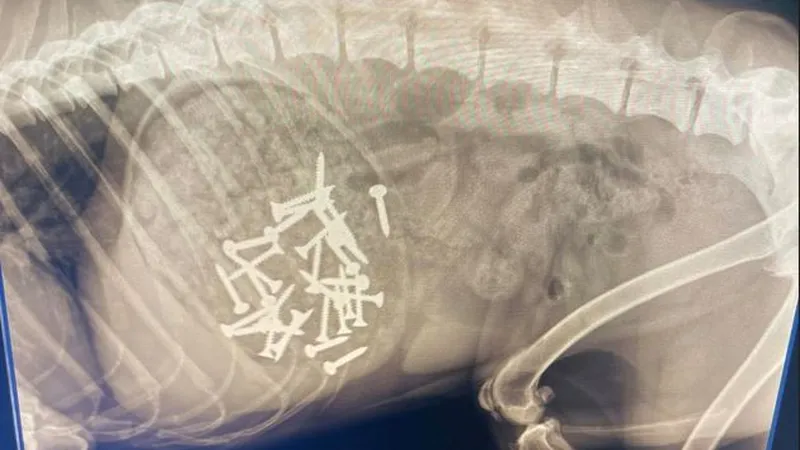

Stéphanie, qui est vétérinaire, a immédiatement pris les choses en main. Elle a soupçonné que son chien et celui de sa voisine Dominique, une jeune chienne Border Collie nommée Ulia, avaient ingéré ces morceaux de viande piégés. Stéphanie a alors récupéré tous les chiens de la résidence et les a emmenés à sa clinique vétérinaire à Lucciana pour passer des radios. Les résultats ont été alarmants : Scooby avait avalé 32 vis et Ulia en avait une dans l'estomac.

Heureusement, grâce à son intervention rapide, elle a pu faire vomir les vis aux deux chiens sans les blesser gravement.